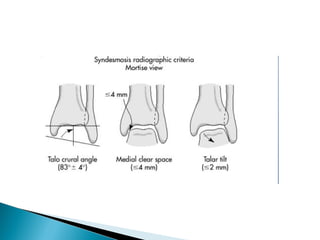

 Medial clear space

◦ Between lateral border of

medial malleous and

medial talus

◦ <4mm is normal

◦ >4mm suggests lateral shift

of talus

•Abnormal findings:

–Medial joint space

widening

–Talocrural angle: <8 or

>15 degrees

–Tibia/fibula

overlap:<1mm